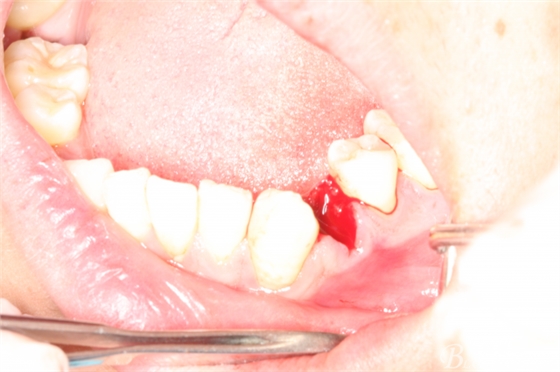

圖20.金剛砂車(chē)針片切44牙冠、消除鄰牙阻力

圖21.片切完成的44牙冠

圖22.微創(chuàng)挺增間隙

圖23.放置牙鉗拔除

圖24.拔除44